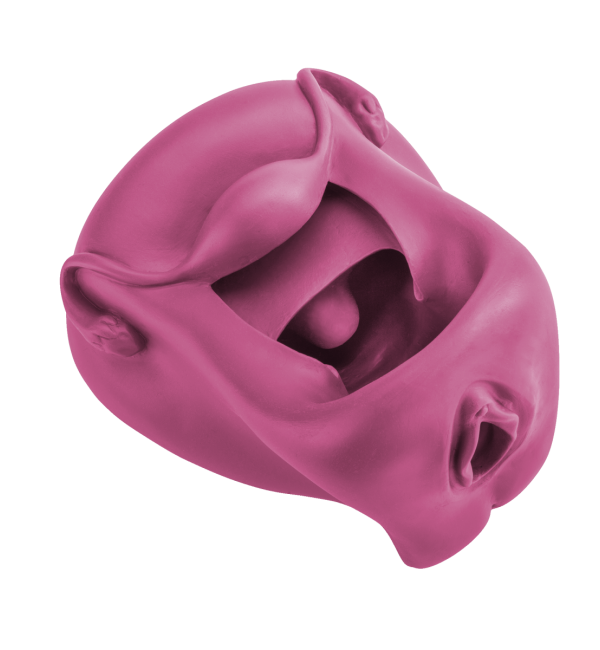

I dilatatori Vagiwell sono dispositivi medici per la dilatazione vaginale in silicone medico, pieni all’interno, in modo da garantire la sufficiente rigidità necessaria all’inserimento ma piacevoli al tatto.

Un’apertura concava ne facilita l’introduzione senza che sia necessario fare leva con un applicatore.

Le 5 misure (integrabili con la sesta, di diametro superiore) favoriscono l’esercitazione progressiva.

I diversi colori facilitano l’identificazione della misura in uso e sono dotati di un comodo astuccio in nylon per riporli.